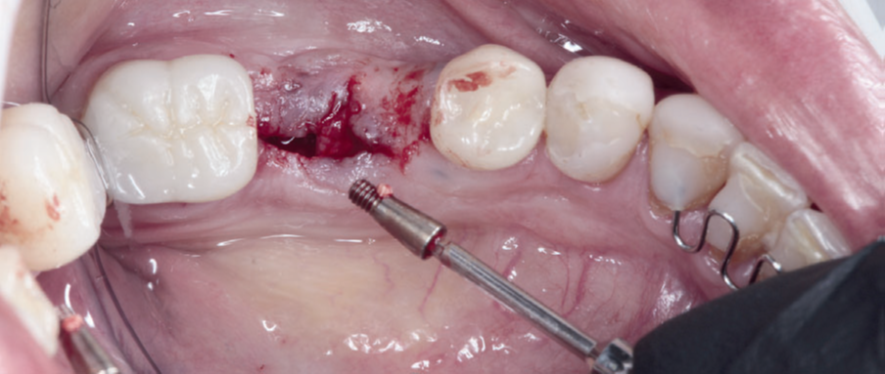

Para a instalação do implante imediato de corpo cônico cone-morse (Maestro, 4 mm x 9 mm, Implacil De Bortoli – São Paulo, Brasil), iniciou-se a fresagem de 9 mm com a fresa lança helicoidal 2.0, seguindo com a fresa cônica 3,5 mm x 9 mm com inclinação para mesial, na região mais centralizada entre a vestibular e a lingual do septo inter-radicular. Com o uso do Túnel Check Cônico 4.0 – instrumental que permite realizar a medição da profundidade da fresagem e sua inclinação –, verificou-se o paralelismo da perfuração para inserção do implante dentário (Figura 4). Em seguida, o implante dentário foi inserido com travamento final de 20 Ncm e recebeu o parafuso de cobertura correspondente (Figuras 5 e 6).